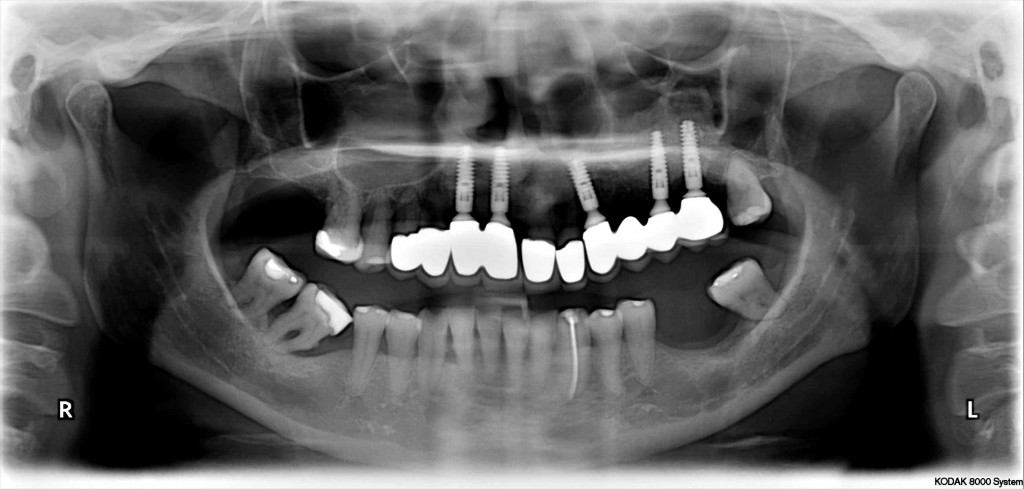

•  DENTAL IMPLANTS

•  FULL MOUTH REHABILITATION